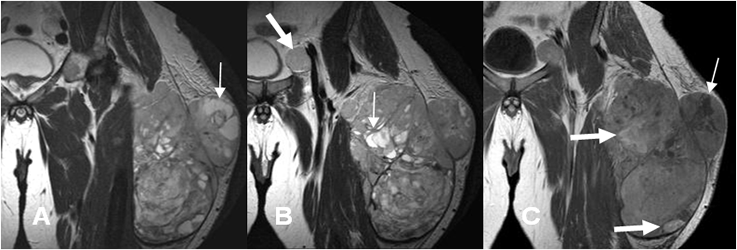

Fig 50 A. Sarcoma pleomórfico indiferenciado.

A y B: RM coronal en T2. Lesión de tejidos blandos, de bordes definidos con una seudocápsula, comportamiento agresivo y 10 cm de diámetro mayor. Muestra señal heterogénea, con algunas zonas quísticas (Flechas delgadas) y adenopatía metastásica inguinal. (Flecha gruesa).

C: RM coronal en T1 con contraste. Gran porcentaje del tumor realza con el contraste, pero se identifican zonas hipointensa, por necrosis. (Flechas delgadas). Existen zonas hiperintensas, por sangrado subagudo. (Flechas gruesas).